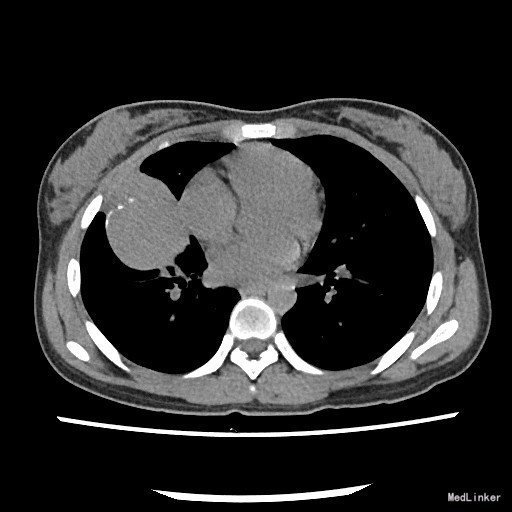

患者:女,18岁 主诉:体检发现右肺结节1月 病史:者1月前体检发现右肺结节1月,不伴咳嗽、胸闷气促、呼吸困难、胸痛、咯血,当时患者因高考未能及时治疗。近期体重无明显改变。

查体:一般情况良好,心肺腹均未见异常。 胸部X片示:右肺结节,性质待定,建议进一步检查。

诊断:肺部肿物(查因?) 治疗:住院后完善相关检查,胸部螺旋CT提示:右肺中叶囊实性肿物,恶性肿瘤待排。排除手术禁忌症,遂于全麻下行胸腔镜辅助下右中下肺叶切除,淋巴结清扫术。术后病理示:粘液表皮样癌。 (右中叶开口肿物)纤维结缔组织内见较多表皮样细胞、粘液细胞及中间细胞,部分形成腺腔样结构,结合免疫组化及特殊染色,符合粘液表皮样癌。 免疫组化结果(②):CEA(+),CK14(灶性+),TTF-1(-),Vimentin(-),CK7(+),Ki-67(2%+),CK5/6(+),P63(+)。 特殊染色结果:PAS(+),d-PAS(+),粘液(+)。